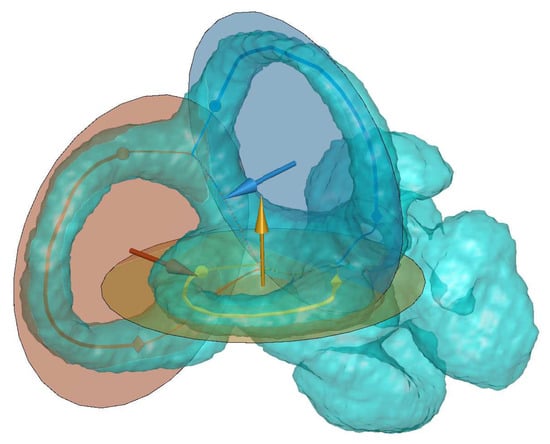

The shape of the ducts was obtained through a skeletonization [17] process of the binarized volume. This name encompasses a broad battery of different algorithms that generate a curve retaining the topology of the original 3D volume (Figure 3). The difference among the various algorithms depends on how this curve is defined.

Although VSK has been tested in numerous geometries, we noted the presence of several artifacts (extra lines) in our working volumes with the parameters specified above due to the ducts complexity and the cochlea presence in the working volume. We reunified redundant points when their mutual distance was smaller than one voxel. In addition, we deleted the cochlea points because they fall out of the scope of this analysis. With these new steps, the merging of all the trajectories generated on the semicircular ducts define the centerline (Figure 3a). Table 2 shows a schematic description of the centerlines definition code.

Based on the proposed method, we computed the centerline for all three SCs of each volunteer’s right ear. From the initial skeleton (Figure 3, top), we removed the common crus structure. The initial SCs centerlines considered in the study are the remaining sections of the ducts: the anterior and posterior ducts paths are defined from the common intersection point to their ampullæ.

Figure 3. Transparent volume of volunteer S18 SCs. Inside the volume, each colored line represent the centerline of one duct: (a) the whole centerline is considered; and (b) the ampulla is excluded from the centerline. The sphere and diamonds correspond to the beginning and end of the retained trajectory (thick line) from the original centerline (thin line). The color encoding is yellow for the horizontal, blue for the anterior and red for the posterior ducts.

Figure 7. Transparent 3D reconstruction of SCs ducts. The solid sphere and diamond represent the beginning and the end of the retained part (continuous thick line) of the original trajectory (thin line) for determining the fitting plane. Each transparent circle represents the fitted plane to each one of the canals. The arrows correspond to the normal vector of each plane. The color encoding is yellow for the horizontal, blue for the anterior and red for the posterior canals.